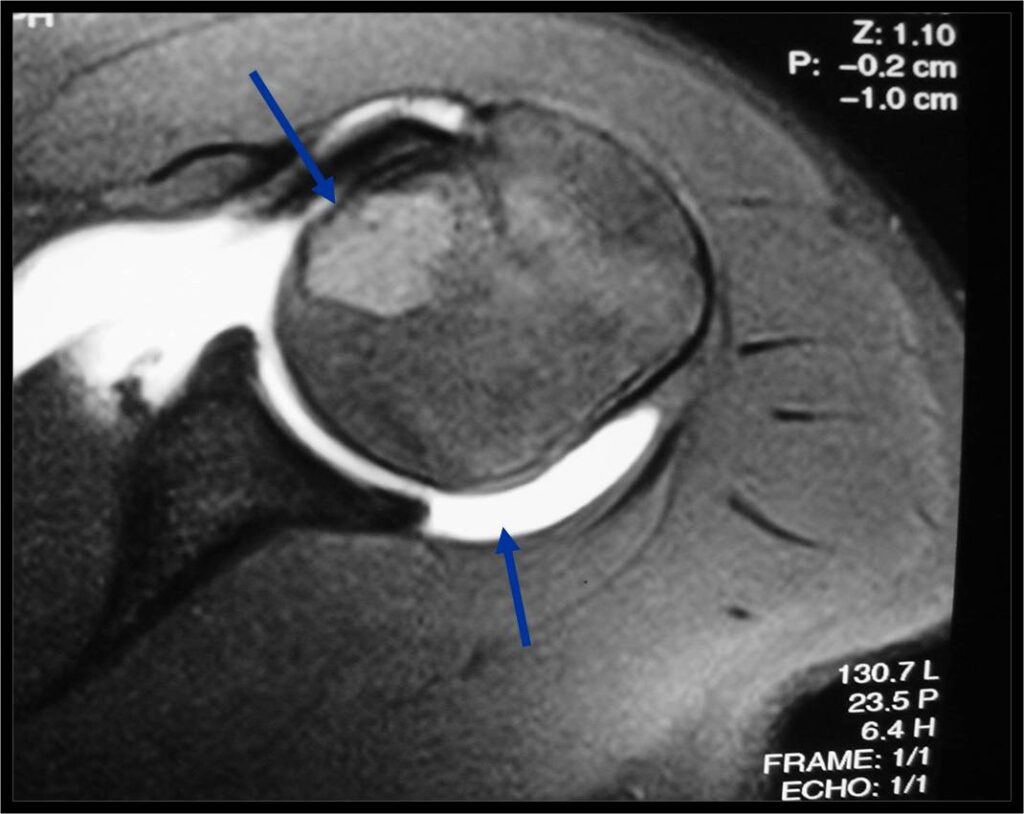

MRI appearance:

- Geographic, well circumscribed lesion in the epiphysis

- Intermediate Signal on T1

- High signal on T2 mixed with low signal areas (low signal areas proposed to be secondary to lysosomal content of highly cellular areas)

- Fluid/Fluid levels demonstrated in tumors that have undergone ABC change (aneurysmal bone cyst change)

- Extensive Surrounding edema is common

- Joint effusion in 30-50% of cases